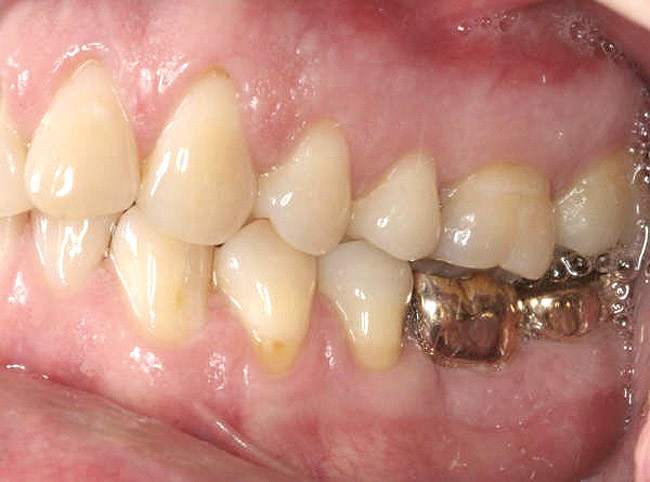

It is also important to explain to patients that the health of their gums is assessed every time they come in; but at this point in time, there are some areas of bleeding on probing, with pockets of disease around their teeth greater than 3 mm deep. It must also be communicated that this is a sign of infection in their gums and that it should be treated immediately (Figure 1).

Figure 1  The crown height is measured from the alveolar crest to the occlusal table.

Figure 1